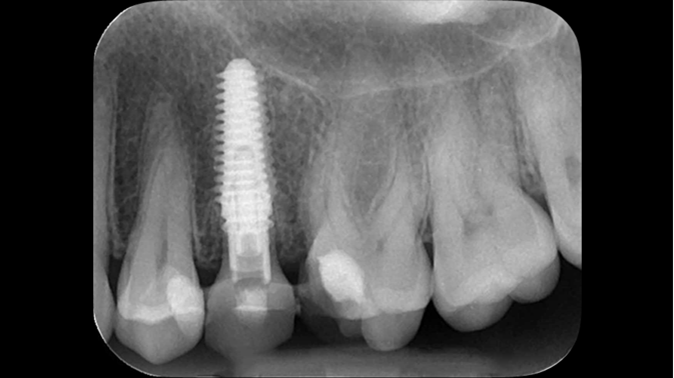

Clinical case: Extraction, immediate implant placement, & provisionalization

- Courtesy of Dr. Iulian Filipov, Romania -

Keywords

AnyRidge, R2GATE, guided surgery, immediate placement, immediate provisionalization, initial stability, Dr. Iulian Filipov, #25, maxillary posterior, immediate loading, Mega ISQ

Products:

AnyRidge implant system, R2GATE, MEGA ISQ, Digital prosthesis